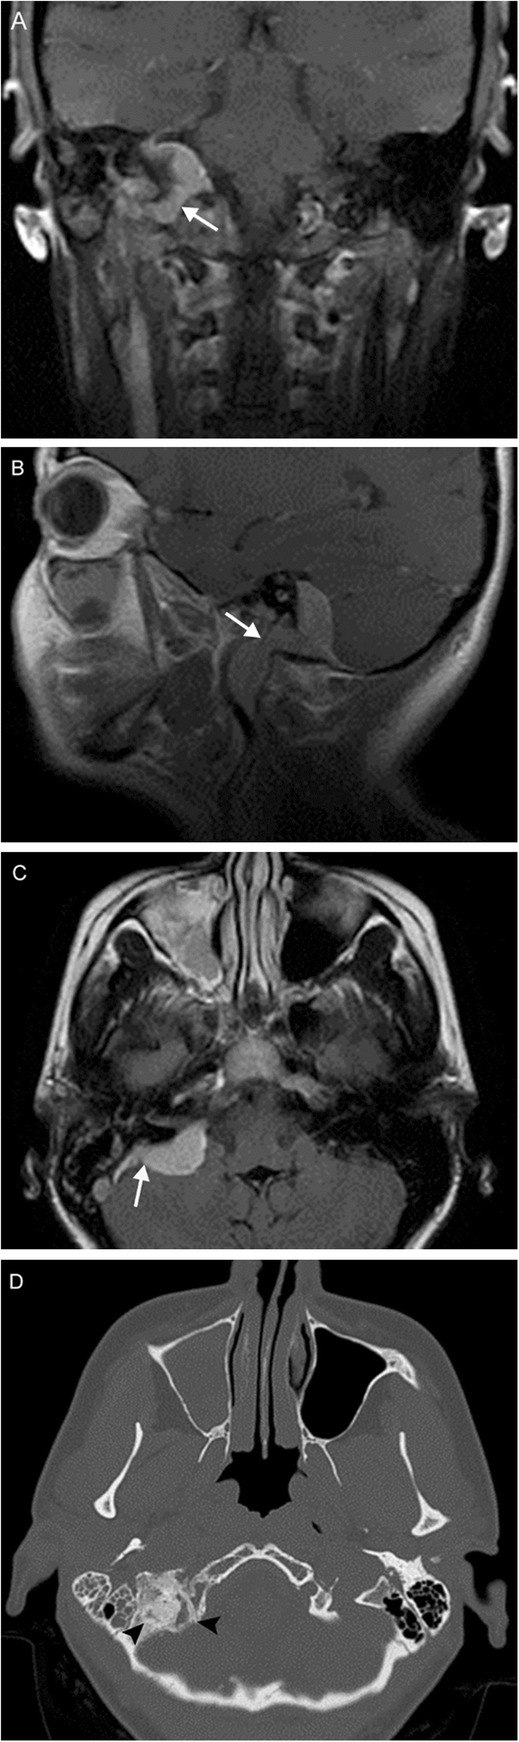

Multiple lower cranial neuropathies should raise the suspicion for a skull base tumor or other lesion, such as an occipital condylar fracture in the setting of trauma. The most common primary tumors are paraganglioma (Figs. 12, 13, and 14), schwannoma, and meningioma (Fig. 15), while the most common metastases (Fig. 16) are from lung, breast, and prostate carcinomas. Other malignancies that can involve the skull base include lymphoma and multiple myeloma.

Fig. 12.

Jugulotympanicum paraganglioma. A 49-year-old woman with voice change and pulsatile tinnitus. Coronal T2-weighted MR images (a, b) and axial contrast-enhanced T1 image (c) demonstrate a T2-hyperintense, enhancing mass centered at the left jugular bulb (white arrows) extending into the hypotympanum (white arrowhead). Axial CT of the temporal bones (d) reveals abnormal soft tissue in the left middle ear (black arrow) with osseous 'moth-eaten' destruction at the jugular foramen (black arrowhead); the cochlear promontory in preserved (not shown). Based on location and appearance, findings are consistent with a jugulotympanicum paraganglioma (glomus jugulotympanicum tumor)

Fig. 13.

Jugular paraganglioma. A 55-year-old woman with relatively sudden onset hoarseness and dysphagia to liquids, who was found to have right vocal cord paralysis on laryngoscopy. Coronal T2 (a) and axial T1 post-contrast (b) MR images reveal a T2-isointense, avidly-enhancing lesion at the right jugular fossa (arrows) extending intracranially, with mild mass effect upon the right cerebellar hemisphere. Foci of low signal (“pepper”) represent flow voids, reflecting hypervascularity. Based on location and appearance, findings are consistent with a jugular paraganglioma (glomus jugulare tumor)

Fig. 14.

Vagal paraganglioma. A 67-year-old man presenting with raspy voice. Sagittal T1 post-contrast (a), axial T1 (b), and axial T2 (c) MR images reveal a T1-hypointense, avidly enhancing lesion with heterogeneous areas of high T2 signal (arrows) centered within the left carotid space. The internal carotid artery is displaced anteromedially (arrowheads). Pathology was consistent with a vagal paraganglioma (glomus vagale tumor)

Fig. 15.

Meningioma. A 45-year-old woman initially presenting with right sensorineural loss, followed by headache, dysphagia, dysphonia, imbalance, and vasovagal syncope. Coronal (a), sagittal (b), and axial (c) post-contrast T1-weighted MR images reveal a dural-based mass at the right cerebellopontine angle (white arrows) extending into the internal auditory canal, as well as through the jugular foramen into the carotid space. Axial contrast-enhanced CT (d) reveals diffuse hyperostosis of the right temporal bone with opacification of the mastoid air cells (black arrowheads). Overall, findings are consistent with a meningioma. Incidental severe right maxillary sinus mucosal thickening is also seen